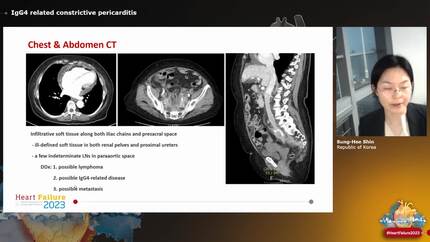

Eosinophilic myocarditis and nonbacterial thrombotic endocarditis in a patient with immunoglobulin G4-related disease